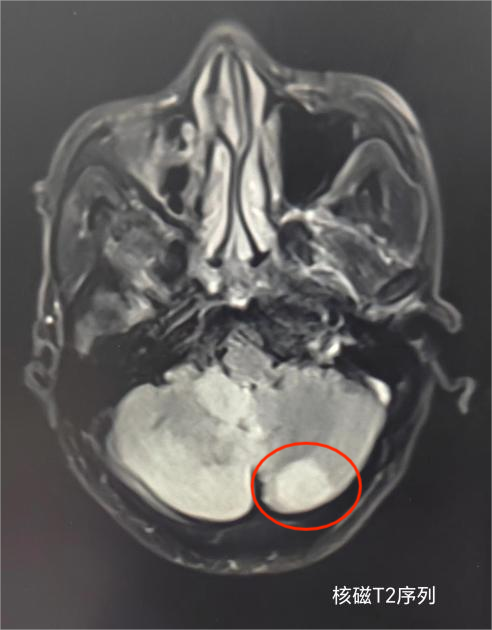

中风患者在我院影像科进行头颅核磁共振检查,发现小脑大面积急性脑梗死影像。